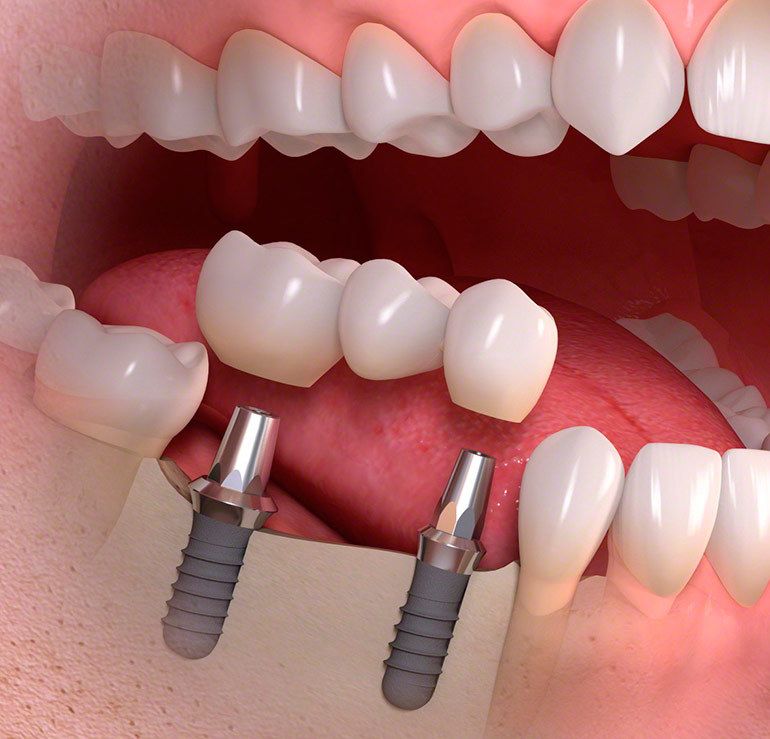

Методика базальной имплантации отвечает всем потребностям пациента и требованиям прогрессивной стоматологии! В отличии от распространенных, в настоящее время, методик ALL ON 4 и ALL ON 6 базальная имплантация не требует "наращивания костной ткани" - импланты подбираются индивидуально под каждого пациента, с учетом особенностей строения его костной ткани.

Применяя методику базальной имплантации мы реализуем концепцию немедленной нагрузки на челюсть (Immediate loading), позволяющей установить протез на импланты в максимально короткий срок - до 3 дней! Методика полностью обеспечивает соответствие современной имплантации и требованиям всех пациентов

all-on-4 и all-on-6 cрок лечения 3-4 дня

Отсутствие одного или нескольких зубов